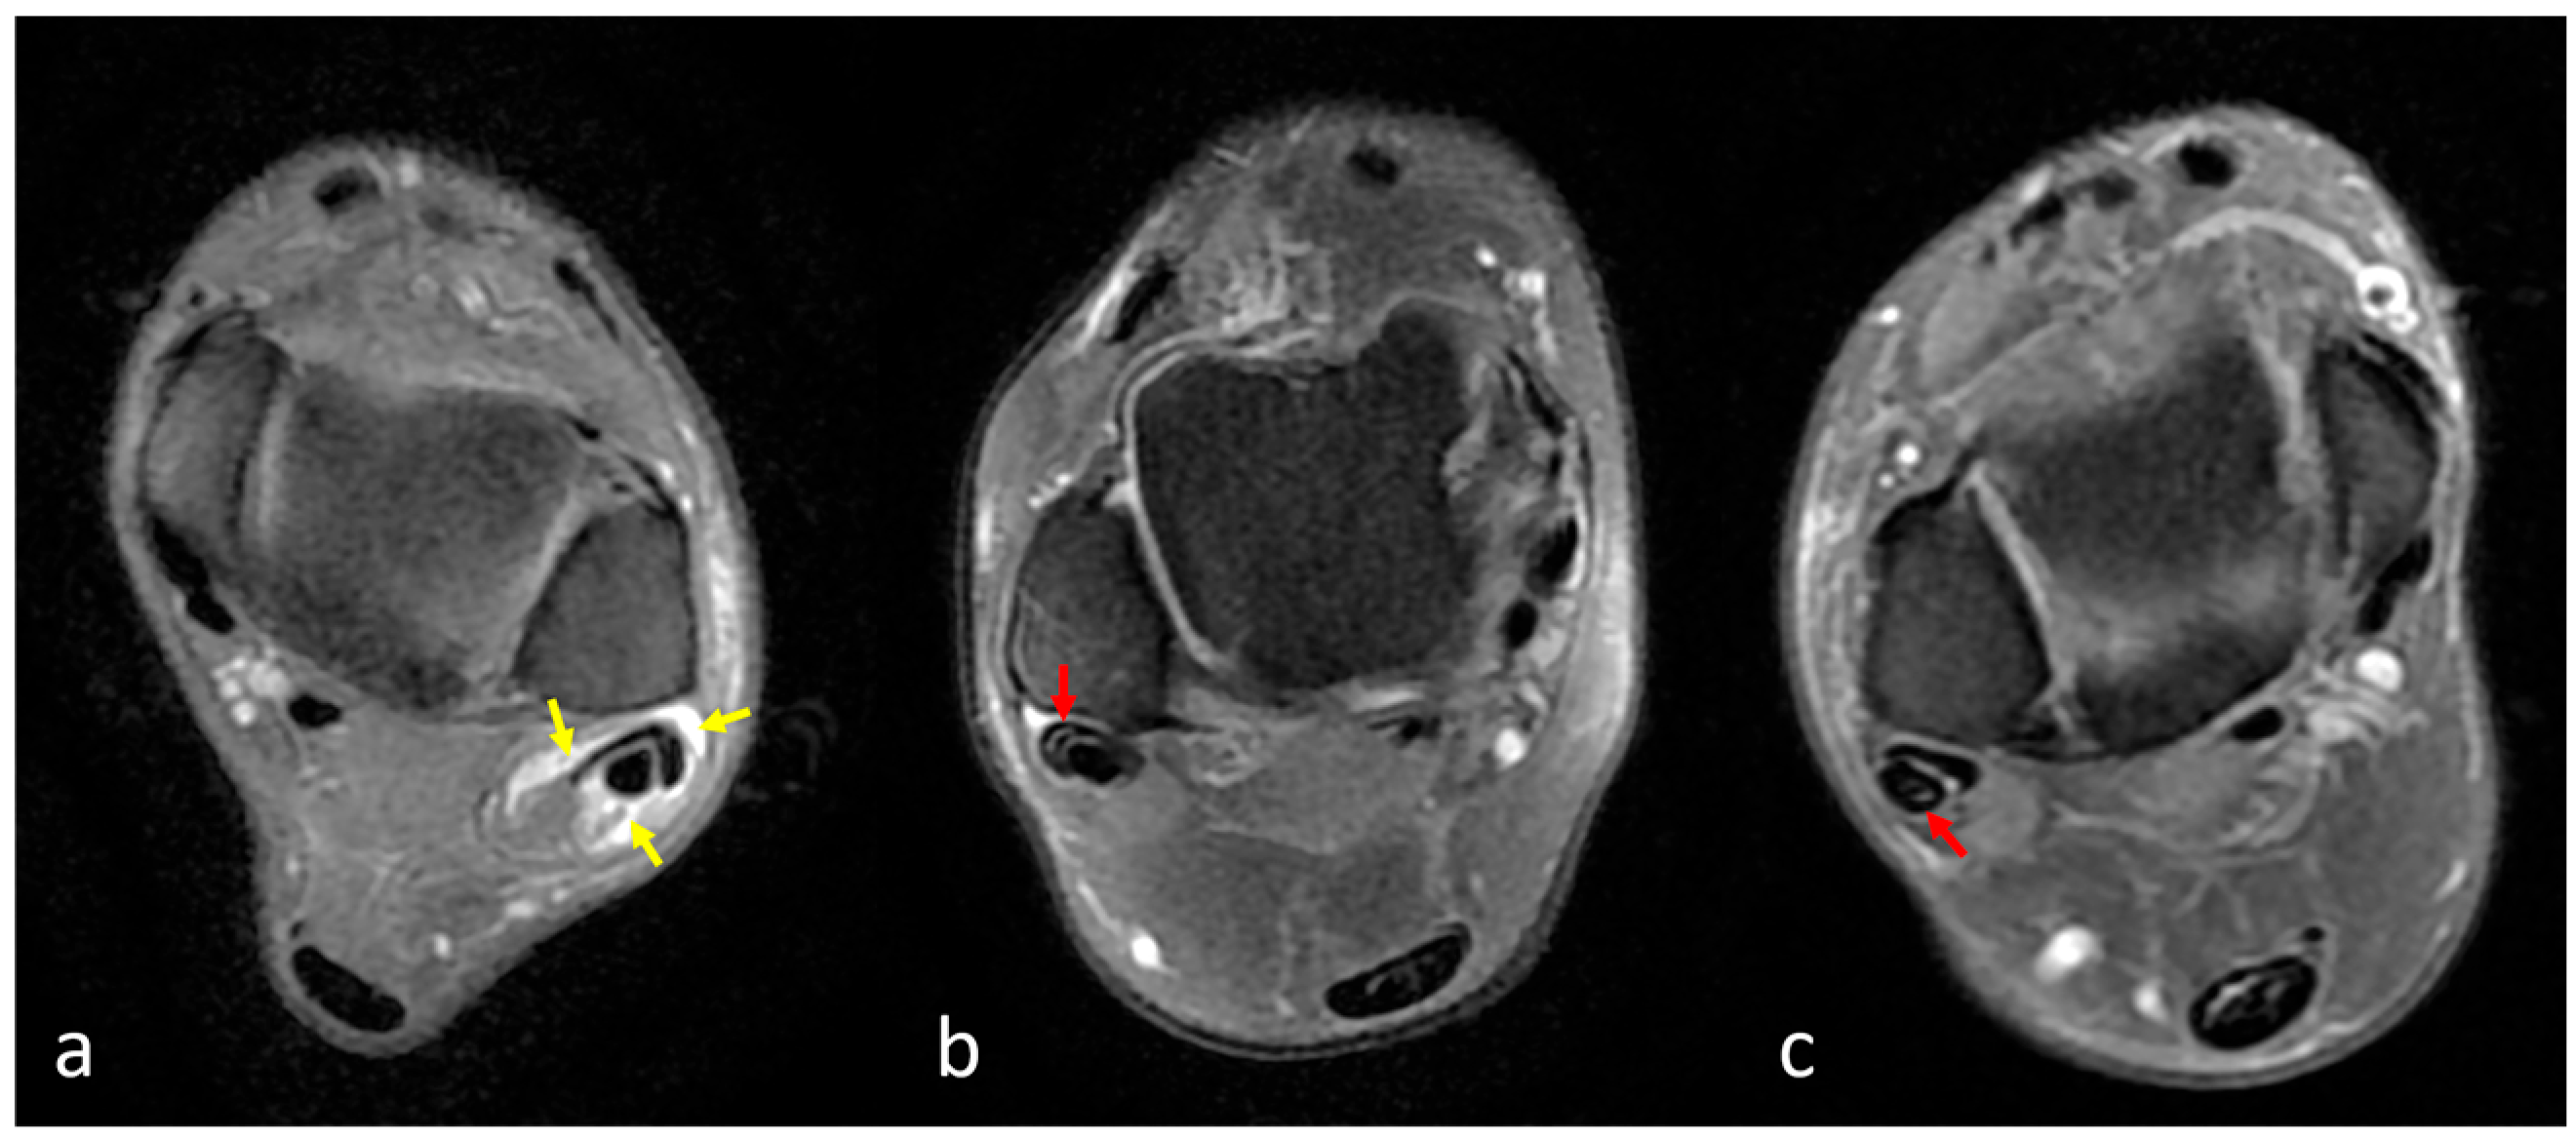

2.3. Assessment of the Peroneus Quartus Muscle and Peroneal Pathologies

2.4. Definitions of Peroneal Tendon Pathologies